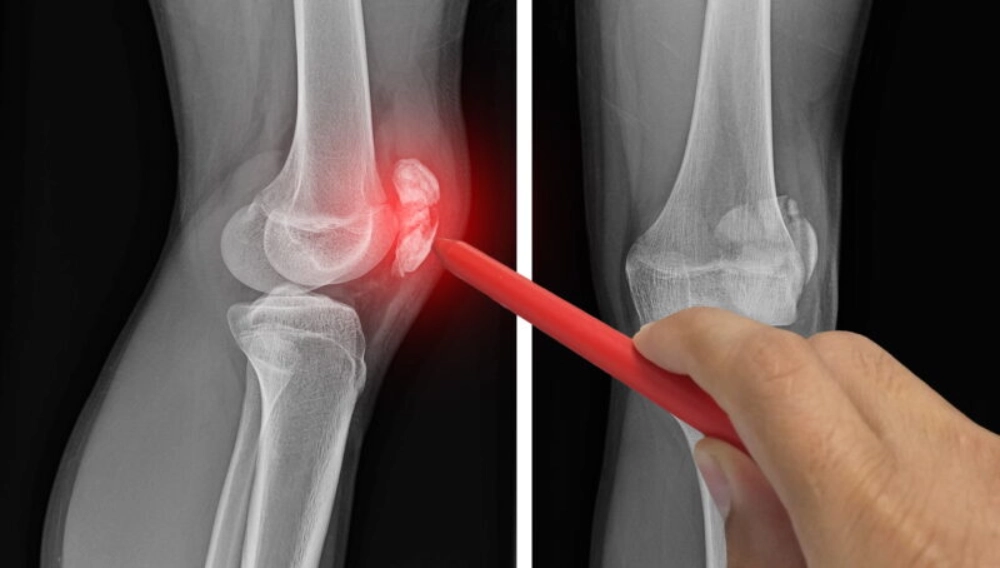

سندرم کشکک دو تکه معمولاً در تصویربرداری‌ های پزشکی مانند رادیوگرافی یا MRI تشخیص داده می ‌شود. این حالت می‌ تواند با درد موضعی، حساسیت به لمس یا محدودیت حرکتی همراه باشد. بسیاری از بیماران تنها زمانی متوجه وجود این عارضه می ‌شوند که به دلیل آسیب یا درد زانو تحت بررسی‌ دقیق قرار بگیرند.

از منظر تصویربرداری، تشخیص تفاوت شکستگی حاد از سندرم کشکک دو تکه ضروری است؛ شکستگی حاد معمولاً خطوط نامنظم با لبه‌ های تیز و بدون کورتکس بالغ نشان می ‌دهد؛ در حالی ‌که سندرم کشکک دو تکه قدیمی دارای حاشیه ‌های صاف و کورتیکاسیون کامل است. انتخاب صحیح بین بی‌ حرکت ‌سازی کوتاه‌ مدت، توان ‌بخشی تدریجی یا در موارد مقاوم مداخله جراحی، به این تفاوت وابسته است.

تصویربرداری رادیولوژیک

رادیوگرافی ساده یکی از ابزارهای اصلی تشخیص است که جدایی قطعات کشکک را به وضوح نشان می ‌دهد. MRI و CT اسکن نیز برای بررسی جزئیات بافت نرم و ساختار استخوانی و سندرم کشکک دو تکه مورد استفاده قرار می ‌گیرند.